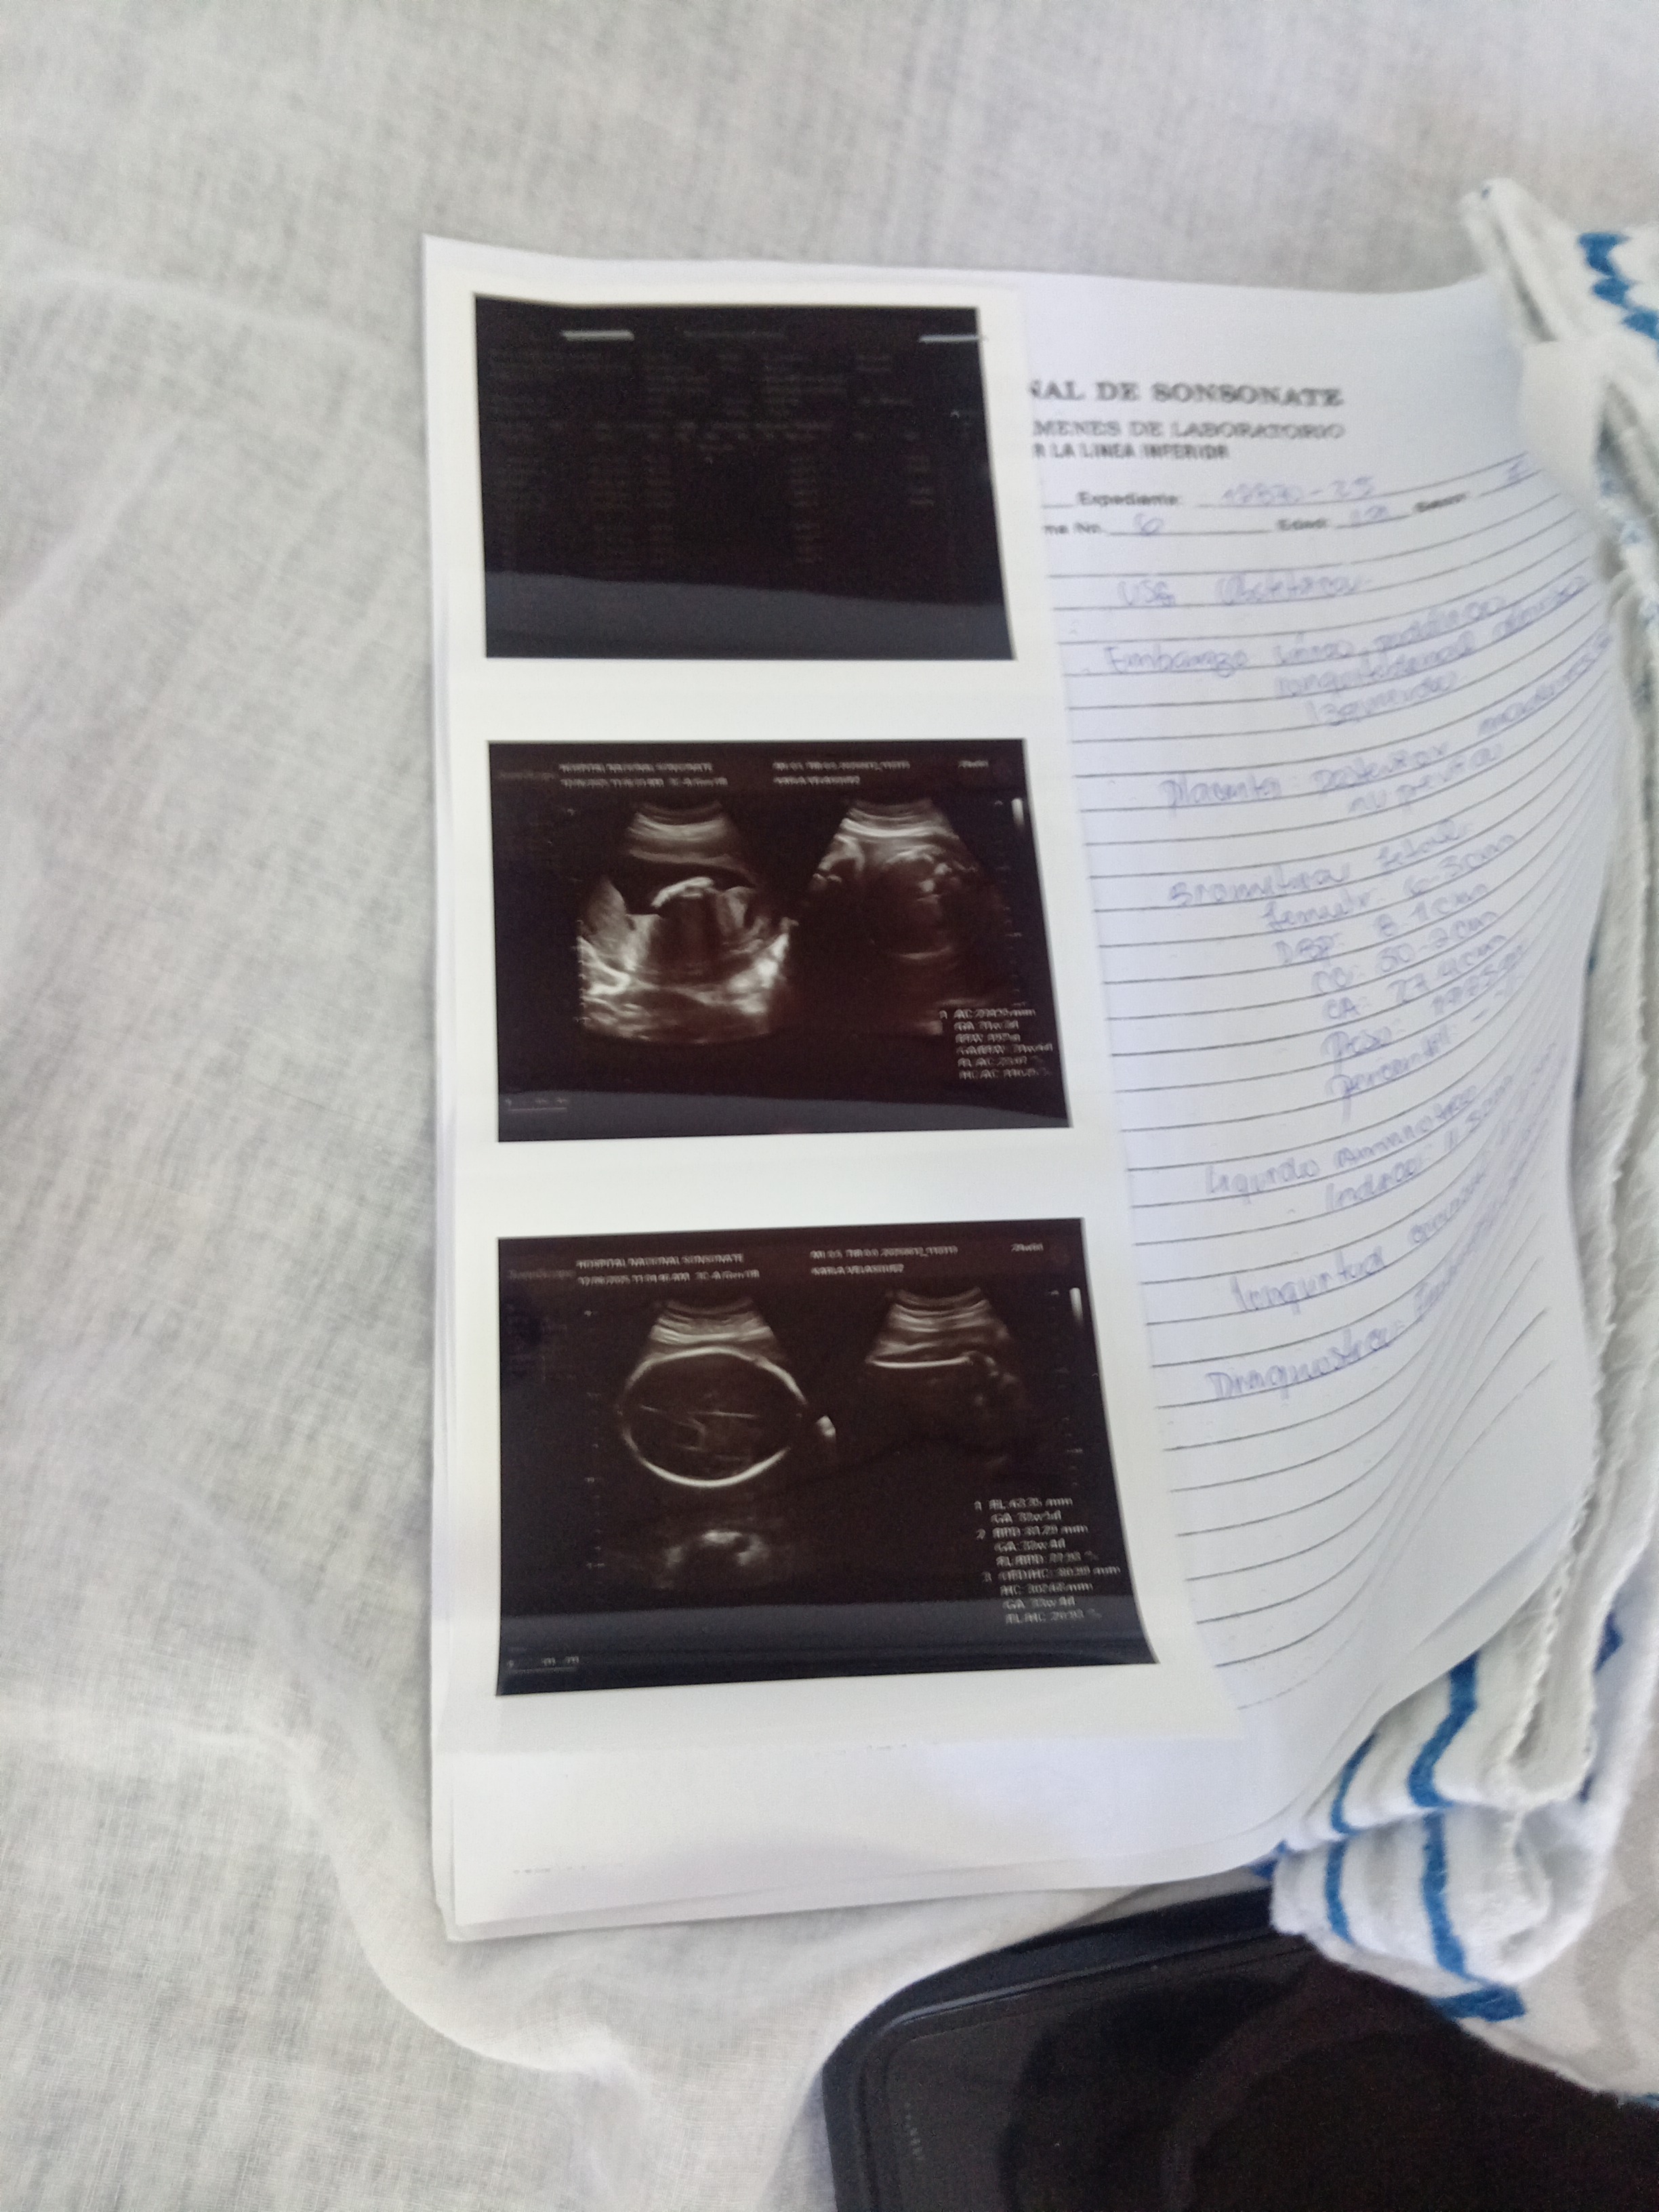

Me llamo Daniel y estoy recaudando para sacar a mi familia a delante, soy de escasos recursos y viene un hijo en camino